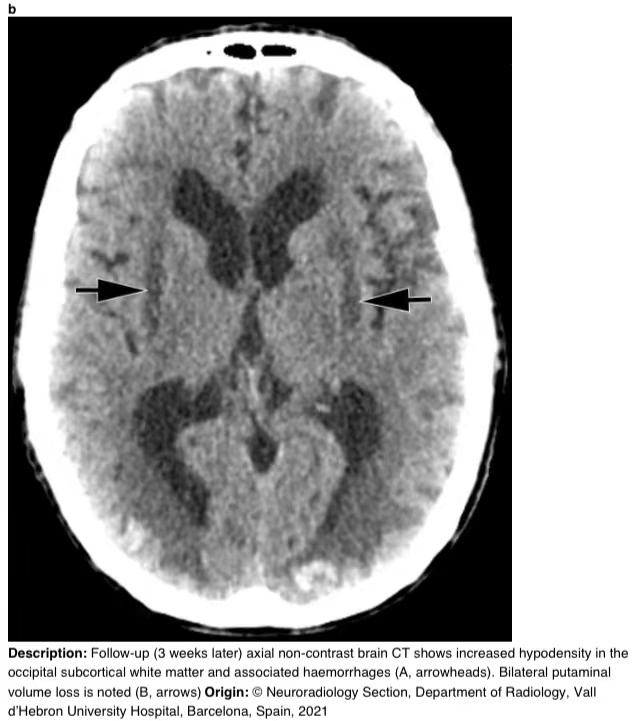

3周后完善的一次新的脑部CT显示,枕下病变的大小增加,并伴有出血性改变(图4)。

图4 a-b 随访(3周后)轴向CT显示枕下皮质下白质低密度增高及相关出血(A,箭头)。可见双侧壳核体积损失(B,箭头)。